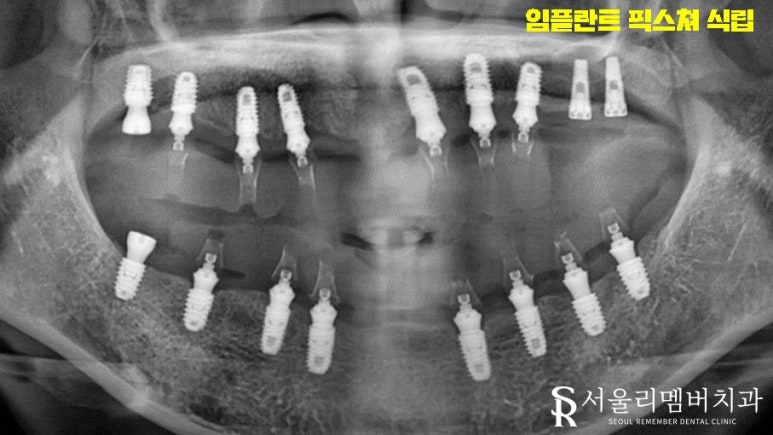

주요 조직과의 관계, 기저질환, 복용약 유무를 꼼꼼히 확인한 뒤에 심어드렸습니다.

묻는 분들이 간혹 계신데요.

꼭 그렇지만은 않습니다. 수술의 난이도가 올라갈 뿐이죠.

올바른 계획과 의료진의 실력만 받쳐준다면 문제없이 진행할 수 있습니다.

식립 개수가 많았기 때문에 기간이 오래 걸렸는데요.

다행히 이수역 치과 환자께서 협조를 잘해주셨기 때문에 예상했던 기간 내에서 마칠 수 있었습니다.

전체임플란트 는 무엇보다 '협조'가 중요하다고 할 수 있죠.

몇 달에서 몇 년까지 걸릴 수 있는 만큼

의사소통, 신뢰가 탄탄히 자리 잡고 있어야 됩니다^^